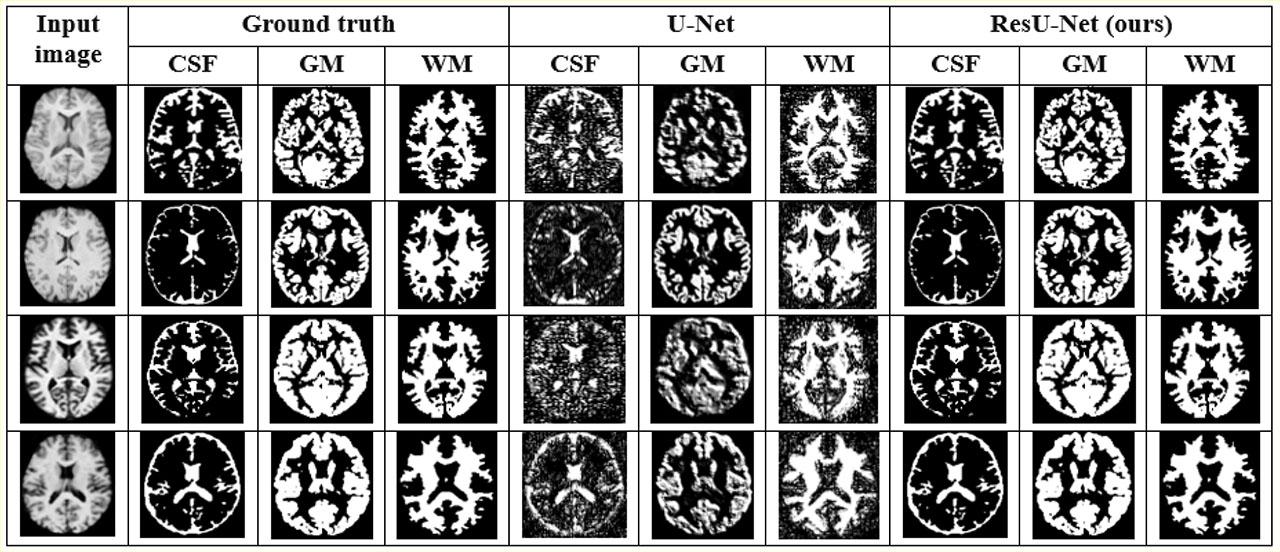

Fig. 2.